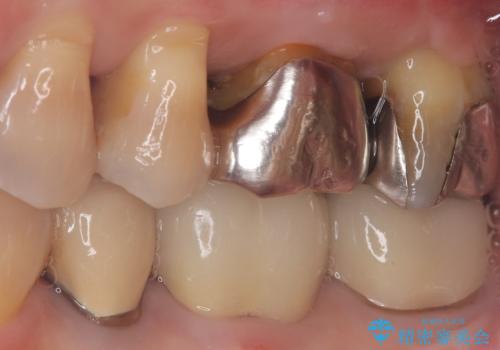

【根管治療】ズーンと痛い歯の治療。

- 奥歯付近がジーンと痛いことを主訴に来院されました。

左上7番の歯は、歯髄検査にて反応を示し、歯周ポケットはありませんでした。

親知らず抜歯を行い、痛みの変化や歯根吸収の有無を確認したのち、抜髄処置を行っています。

症状改善し、遠心の骨の回復も認めます。

バイオセラミックシーラーを使用して根管充填を行っています。